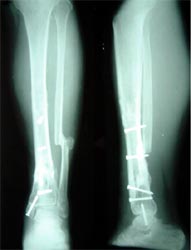

病例二 患者男性,45岁,胫骨上段开放粉碎骨折2年,骨不连

图2-1病例二、患者男性,45岁,胫骨上段开放粉碎骨折2年,骨不连。我们用带锁髓内钉固定骨折端提供支撑力,患者自体骨髓细胞经与松质骨和骨生长因子复合,使没有细胞的植骨材料变成了有细胞的活骨。骨折在9个月后愈合。